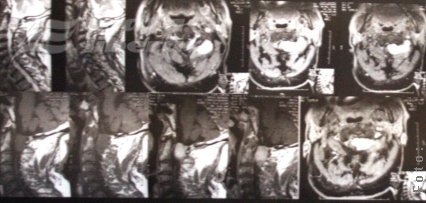

Primul caz este al unui gălăţean de 70 de ani care, înainte de intervenţie, suferea de tetrapareză, adică nu-şi mai putea folosi nici mâinile, nici picioarele. Cauza era o tumoră care îi comprima măduva spinării şi care a fost depistată cu ajutorul investigaţiei RMN.

Foto: Aşa arăta, la investigaţia RMN, coloana vertebrală a bărbatului de 70 de ani, suferind de tetrapareză